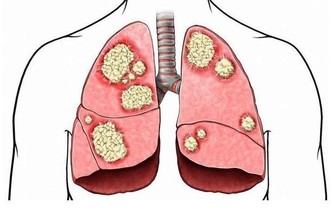

6. 不做篩檢的人

雖然大腸癌盛行率不斷攀升、發生率高,但它一般來說,是能被早期發現、早期治療的,且治愈率高。

因為大腸癌大多數都是因為腺瘤性息肉經過5~10年後演變而成,只要定期篩檢,便能防患於未然。

建議: 50歲以上的人群,每年進行一次糞便潛血檢查,如果有排便異常,則要及時進行腸鏡檢查。